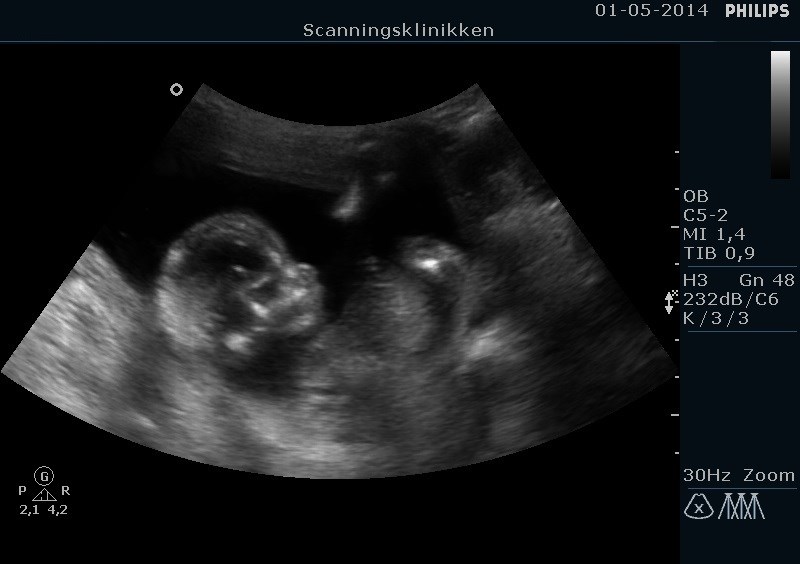

Her er min lille stjerne (16+1)

Vedhæftede fotos (klik for at se i fuld størrelse)